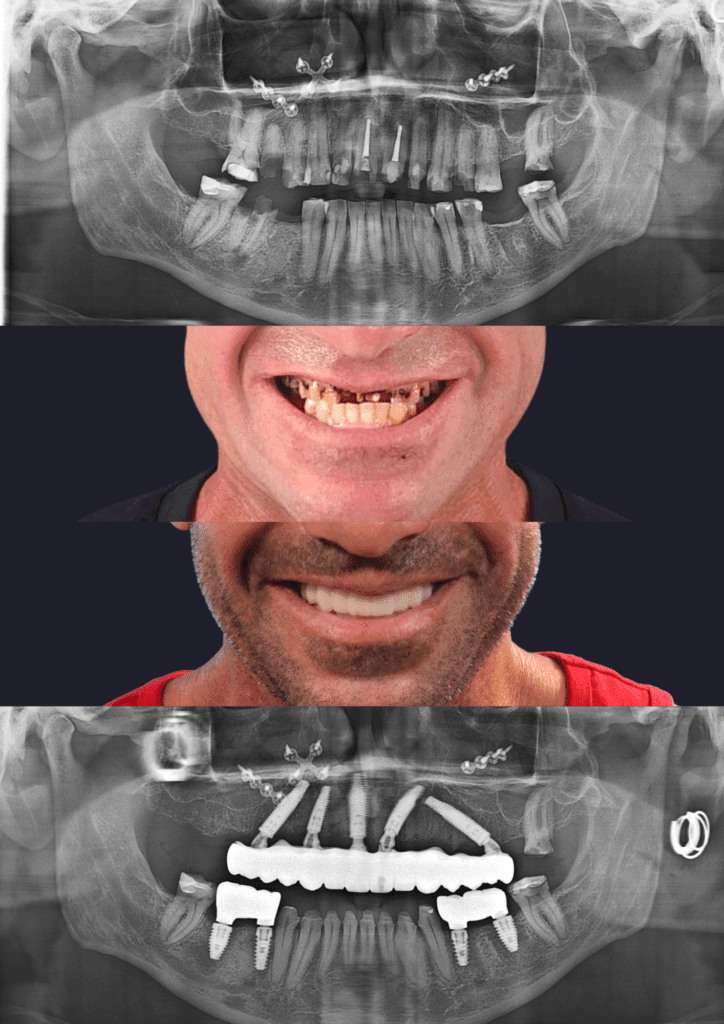

Before & After Treatment Gallery

The photos shown here document completed full-jaw implant treatments. Each case involved detailed planning, surgical placement of implants, and a custom-made fixed bridge. Treatment outcomes, timelines, and suitability vary and are assessed on a case-by-case basis.